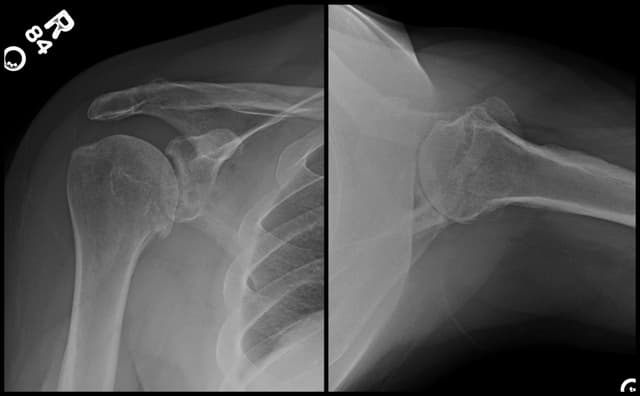

Imaging

Pre-op